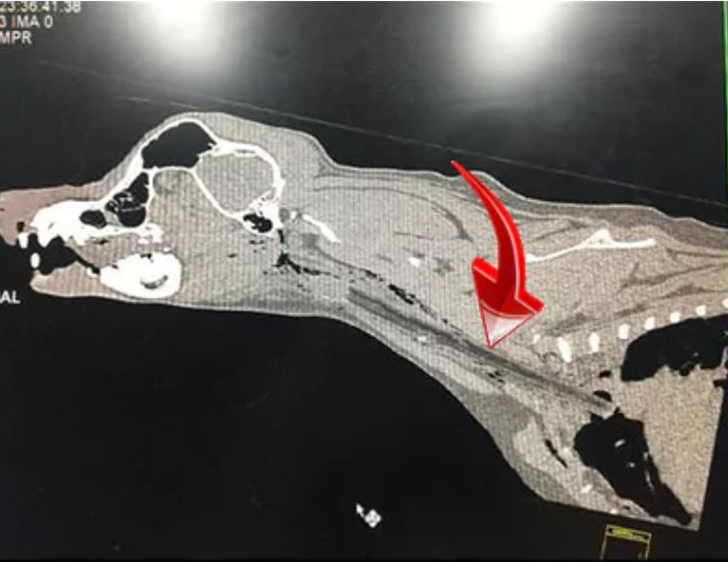

대시가 걱정되었던 가족들은 대시를 동물병원으로 데려갔습니다. 그리고 동물병원에서는 대시가 입 주변가 목 뒤쪽에 통증을 느끼고 있다고 판단했죠. 이후 이들은 엑스레이를 찍어보았는데요. 엑스레이 사진을 본 이후 경악할 수밖에 없었습니다. 바로 흉부 입구로 가는 후두부를 따라 큰 막대기로 추정되는 단단한 이물질을 보았기 때문입니다. 이뿐만이 아니었습니다. 대시의 혀는 관통상을 입었는데요. 곧 이 이물질을 제거하는 수술을 받게 되었습니다.

과연 이 막대기는 어떻게 대시의 몸 속으로 들어가게 된 것일까요? 바로 주인과 막대기를 쫓으며 놀았기 때문인데요. 강아지는 막대기를 물기 위해 전속력으로 달려가는데 만약 막대기가 강아지의 입에 정면으로 들어가면 막대기가 강아지의 혀를 통과해 목구멍으로 들어가는 것이죠.

다행히 대시의 경우 막대기가 가슴 바로 안쪽에 멈춰 심장이나 폐에 구멍을 내지 않았지만 더 심각한 경우에는 이런 막대기로 인해 감염이 일어나 건강과 생명에 큰 영향을 미칠 수 도 있다고 합니다. 그리고 동물 응급실에는 이런 일을 당한 강아지들이 꽤 자주 온다고 하는데요. 절대 막대기를 가지고 놀지 않고 공이나 고무 장난감을 가지고 노는 것이 훨씬 안전하다고 전하고 있습니다.